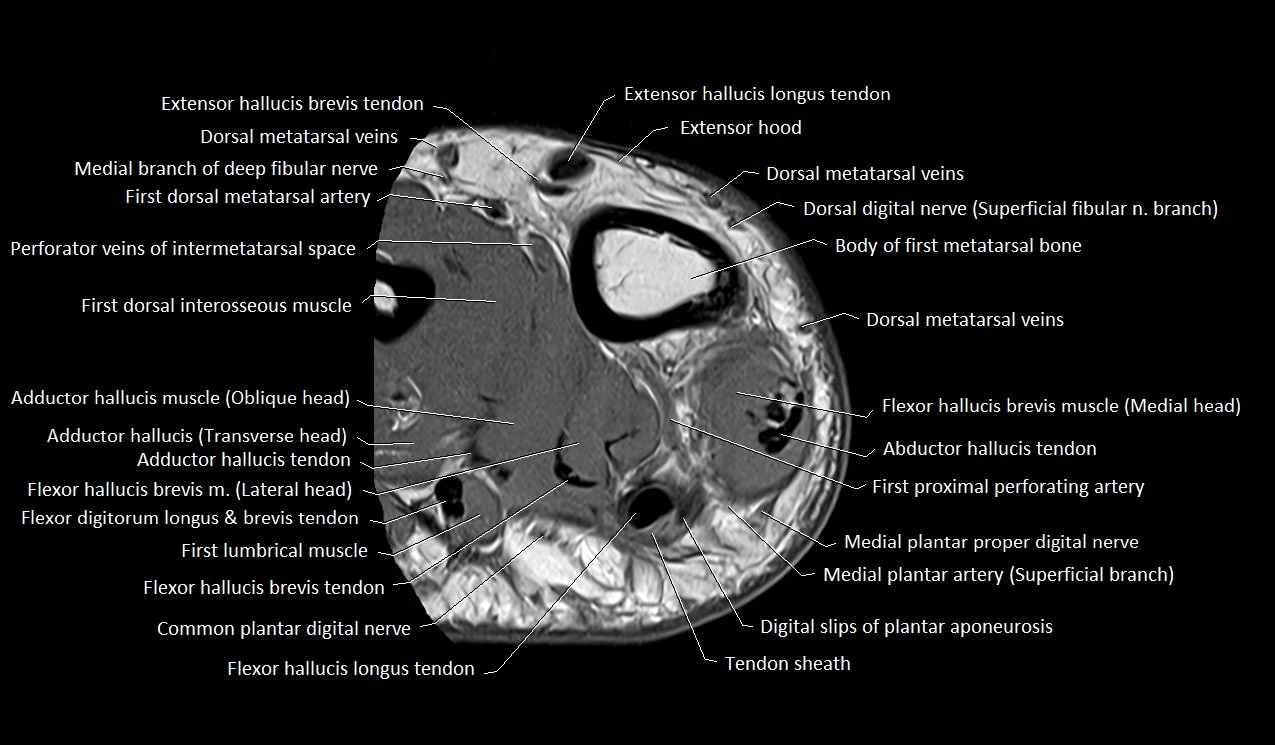

MRI image

image